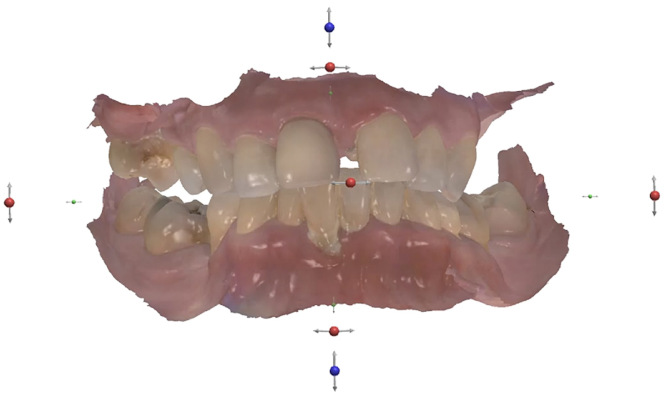

Fig. 2

No abnormalities were found during the extra-oral examination. The patient presented with a low smile line. The intra-oral examination revealed terminal dentition due to generalised periodontal disease. The patient presented with severe resorption of the posterior maxilla bilaterally (Fig. 1). The radiographic examination showed generalised alveolar bone resorption with vertical bone defects (Fig. 2).